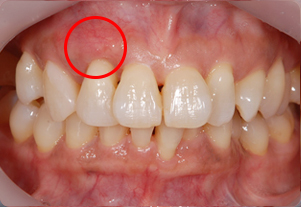

症例2(歯肉移植)

Before

After

- POINT

- 右上2番(赤丸の箇所)の歯茎が下がってしまった患者様です。

歯茎が薄く歯もしみてしまい歯磨きしにくいため、上あごから歯肉を移植しました。

厚みのある歯茎になり、しみる症状も改善されました。